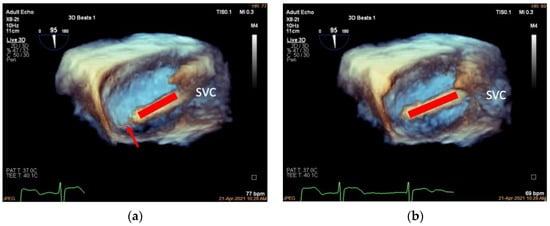

3.6. Assessment of Clutch Status